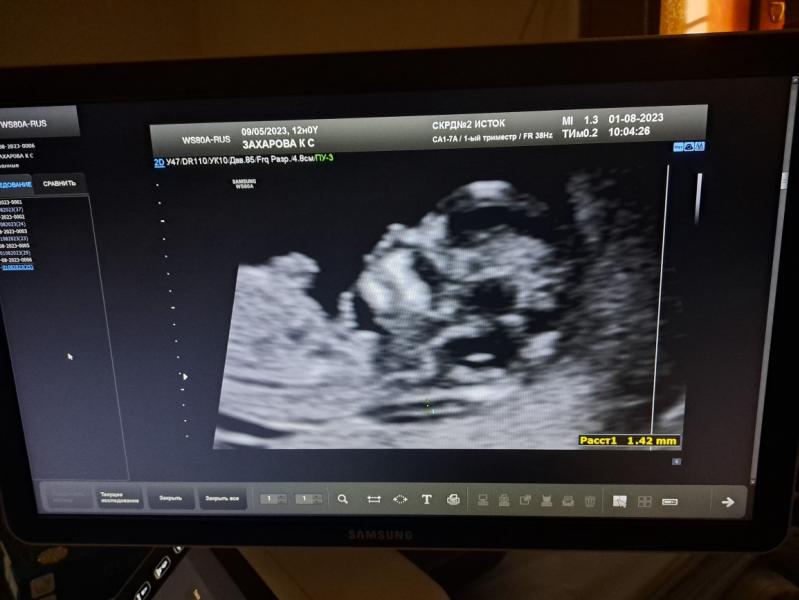

Сегодня была на 1 скрининге,переживала очень

Сказали все отлично, терапевт обрадовал, что анализы все в норме, единственное, что низко расположена плацента, но это не страшно

Пол решили еще не узнавать, всего 80-90% виден, пойду в 15 недель узнаю и будем делать Гендер Пати!